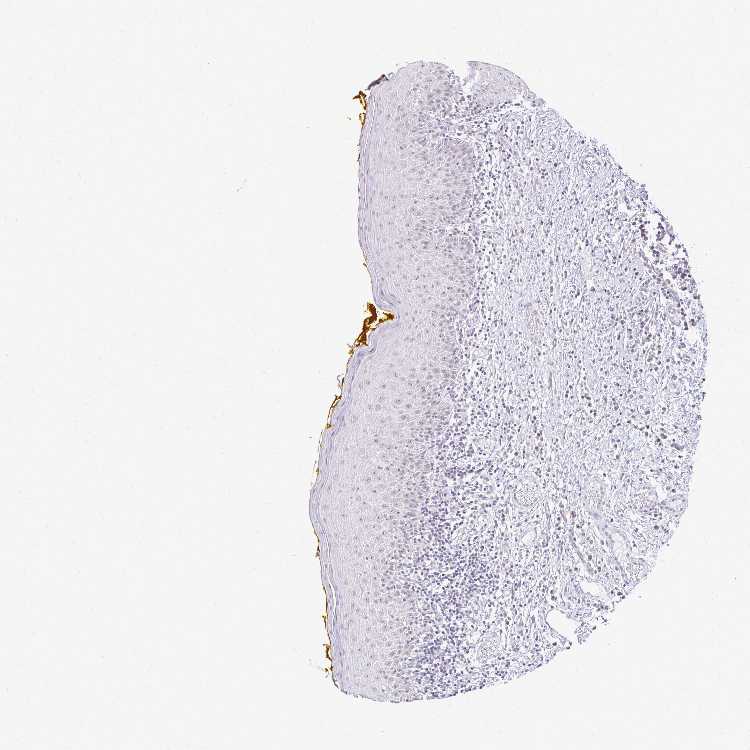

PLCB1